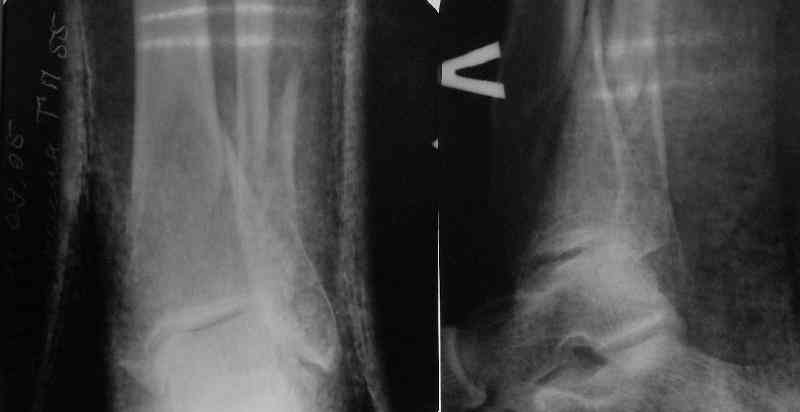

Very interesting application, but is the final position in a little distal varus with some fibula

distraction? Would that have been eliminated by fibula plating?

TDVC> Very interesting application, but is the final position in a

TDVC> little distal varus with some fibula distraction?

At least both the ankle mortise and tibial alignment look acceptable, don't they?

I am just trying to illustrate that prevention of 1)tibial valgus and 2)loss of reduction can be provided without fibular plating. Small changes of conventional nailing techniques allow to maintain reduction of the tibia reliably without adjunctive fibular stabilization.

In delayed cases acute length restoration performed only in the tibia may leave the fibula shortened thus change the mortise. So it is reasonable to restore length of both bones simultaneously by distractor and fix the fibula not with open reduction and plating but just by a single perQ screw. Example attached.